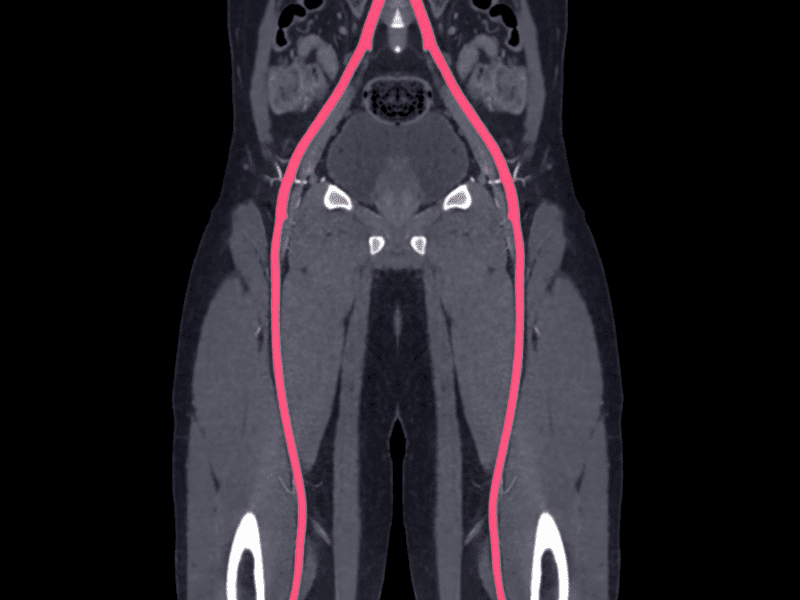

L’arteriopatia napoli è una condizione che coinvolge il restringimento o il blocco delle arterie, che può compromettere il flusso sanguigno e causare gravi complicazioni.

- Bypass arterioso: Nei casi più gravi, un intervento chirurgico per creare una nuova via per il flusso sanguigno, bypassando le arterie ostruite.